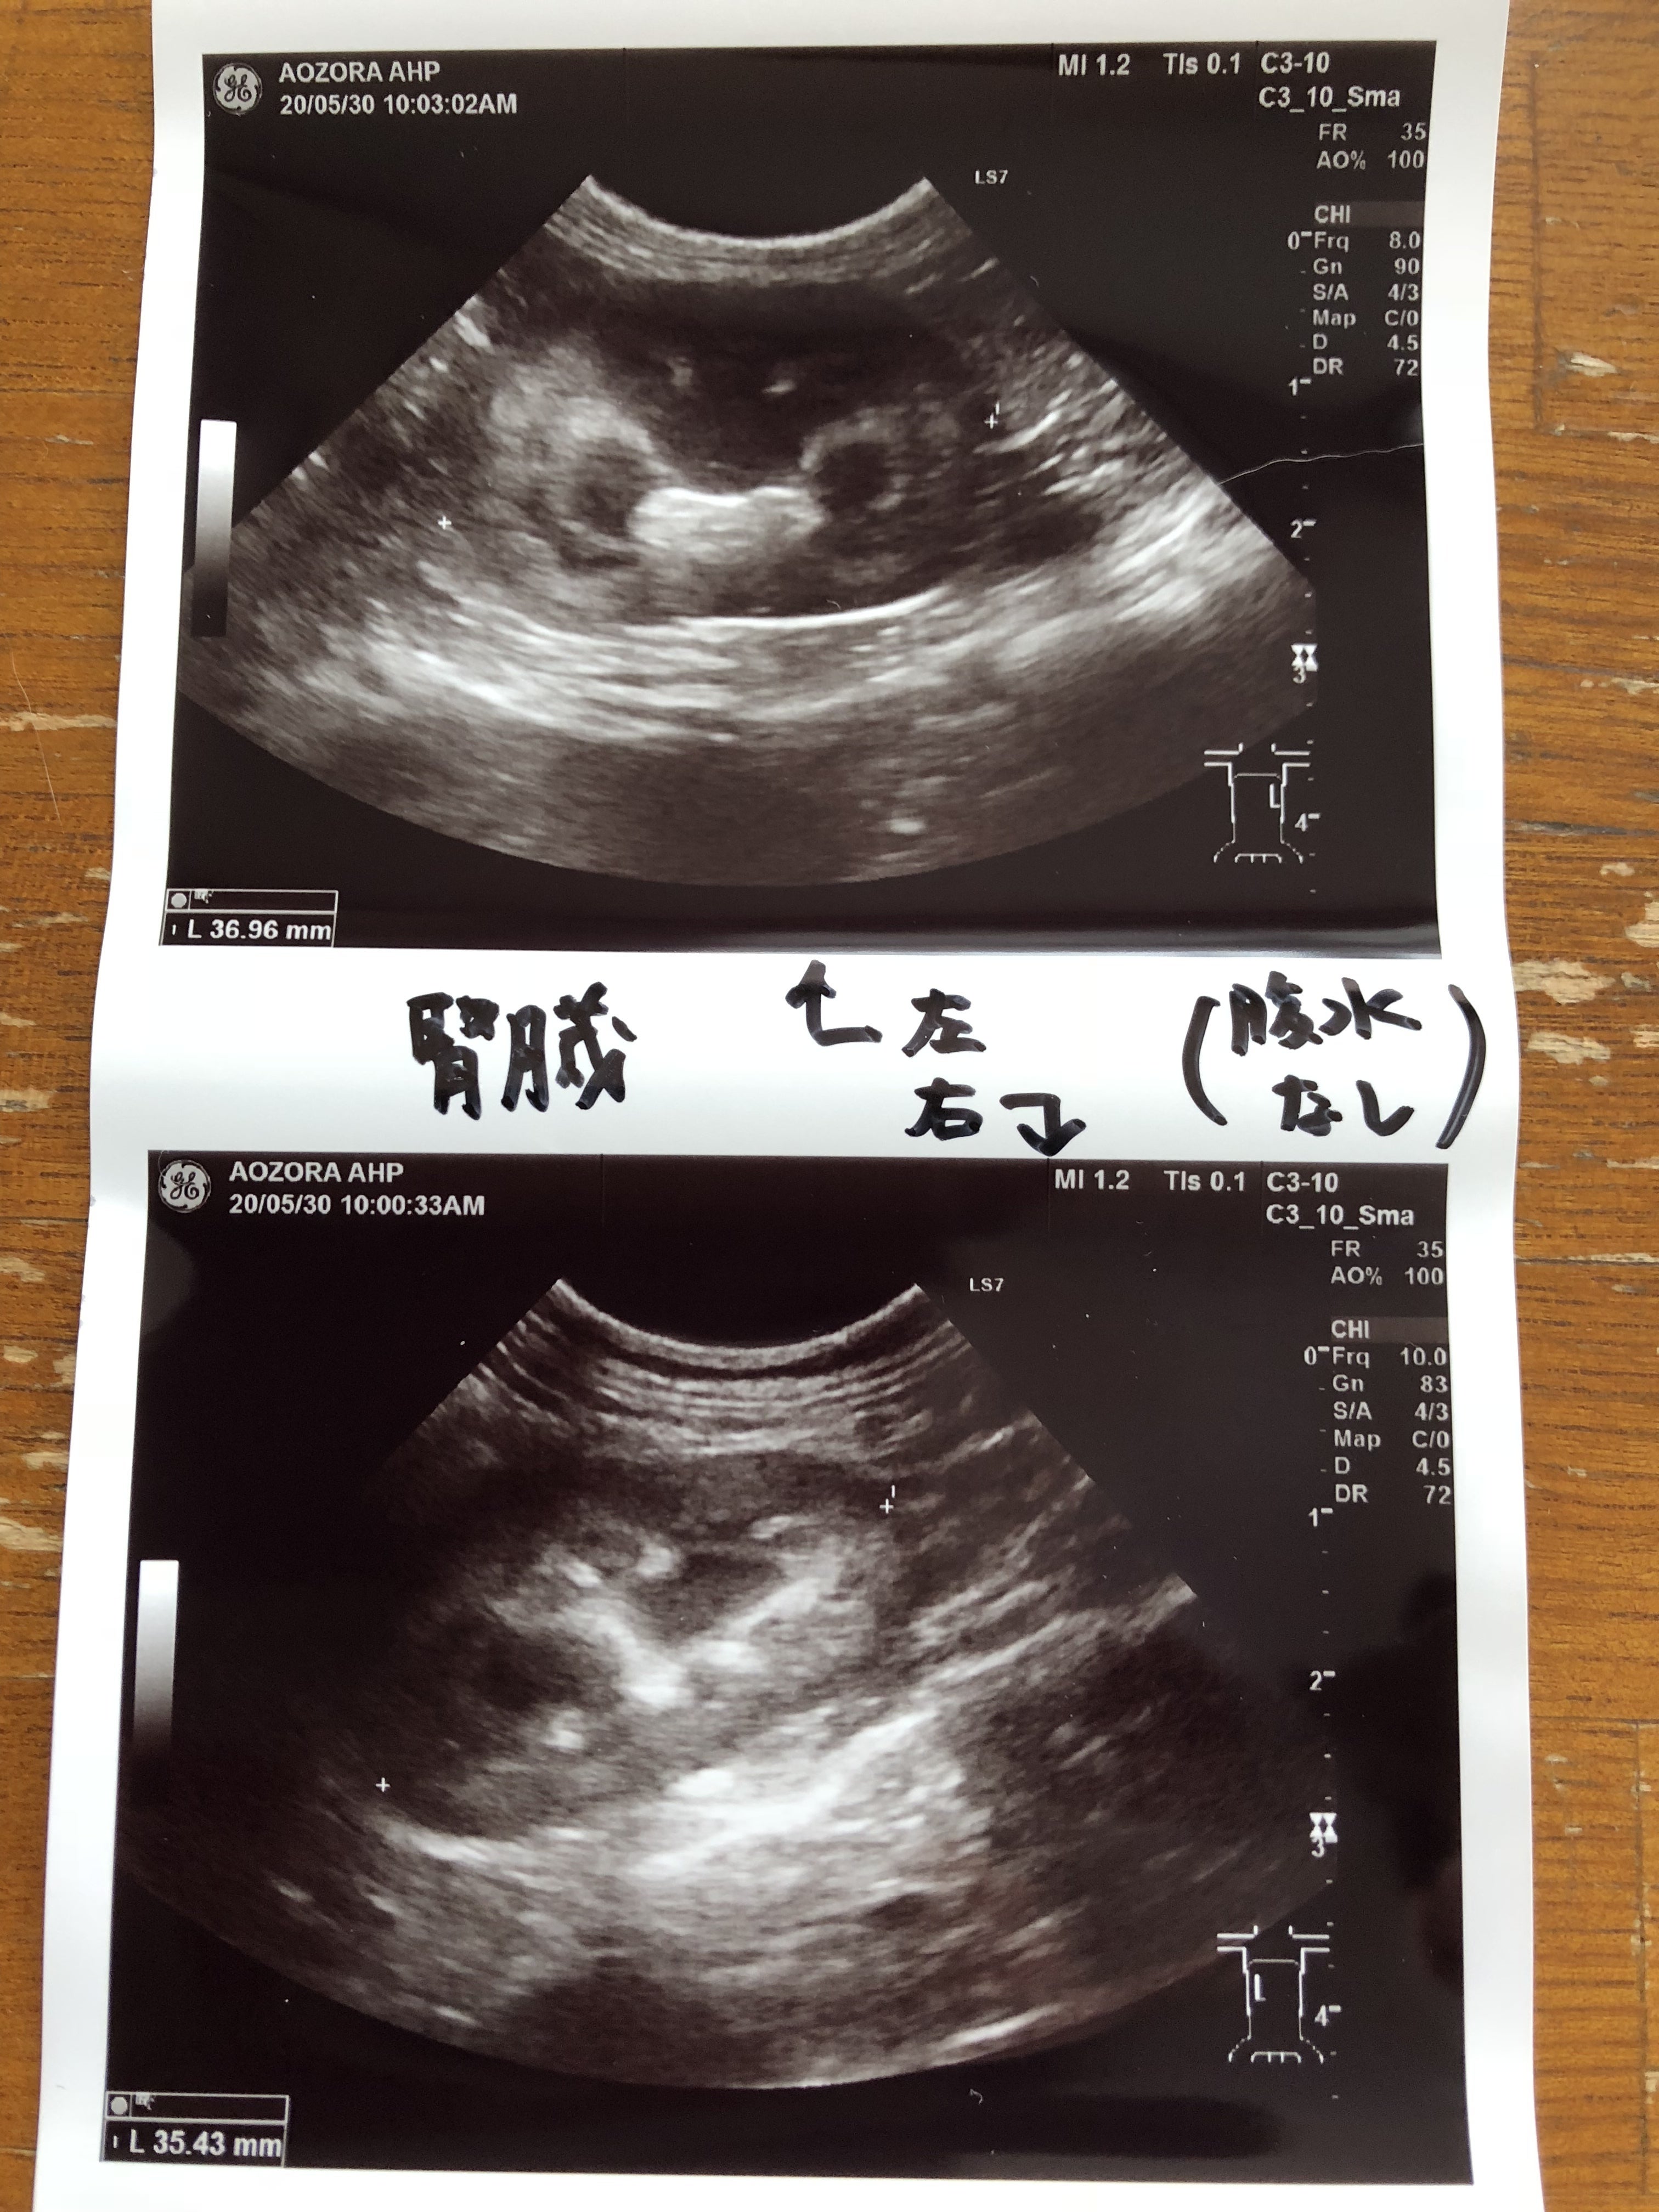

エコーの検査結果です。腹水も無く、リンパ節の腫れも見当たらず、異常は無いとの事でした。